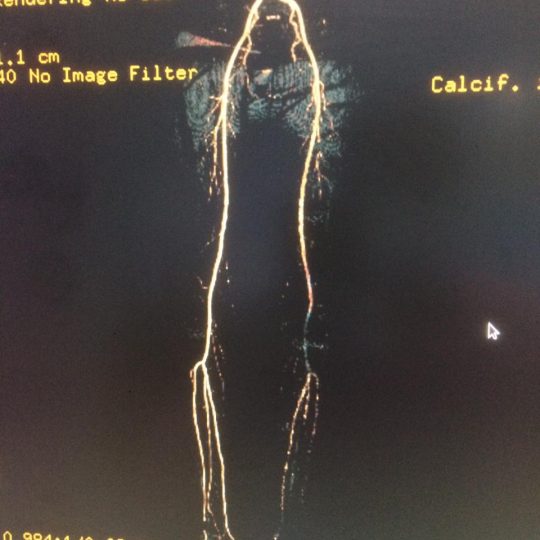

Patient’s Successfully Treated with Diabetic Foot Problems